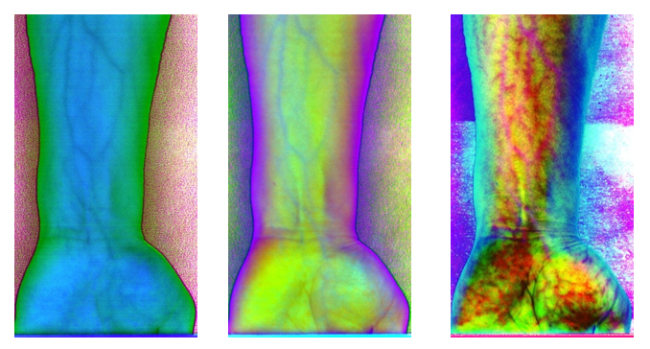

為了更客觀真實地識別出手臂靜脈,根據(jù)波段組合的特點,對PCA前六個主成分組合成各種假彩色圖像,如圖10為手臂正面的假彩色合成圖像,圖11為手臂反面的假彩色合成圖像。與灰度圖相比,假彩色合成更能直觀地識別出手臂靜脈。

圖10 手臂正面PCA假彩色合成圖像

圖11 手臂反面PCA假彩色合成圖像